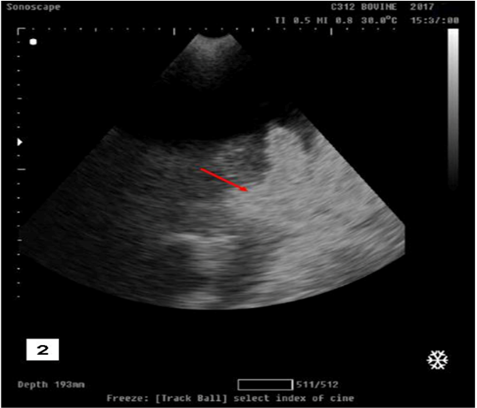

Figure 2

Ultrasonographic image showing free anechoic fluid in the abdominal cavity which representing urine from a ruptured bladder with the presence of hyperechoic floating substance (arrow) representing fibro gelatinous material results from the reaction of the urine with the peritoneal cavity in buffalo calf with urine retention and had ruptured urinary bladder.